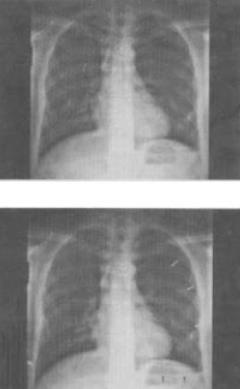

- 单项选择题 患者男,18岁,被人殴打后胸痛,结合胸片,最可能的诊断是()。

A、血气胸

B、气胸

C、胸腔积液

D、肺气肿

E、肺挫伤

- A